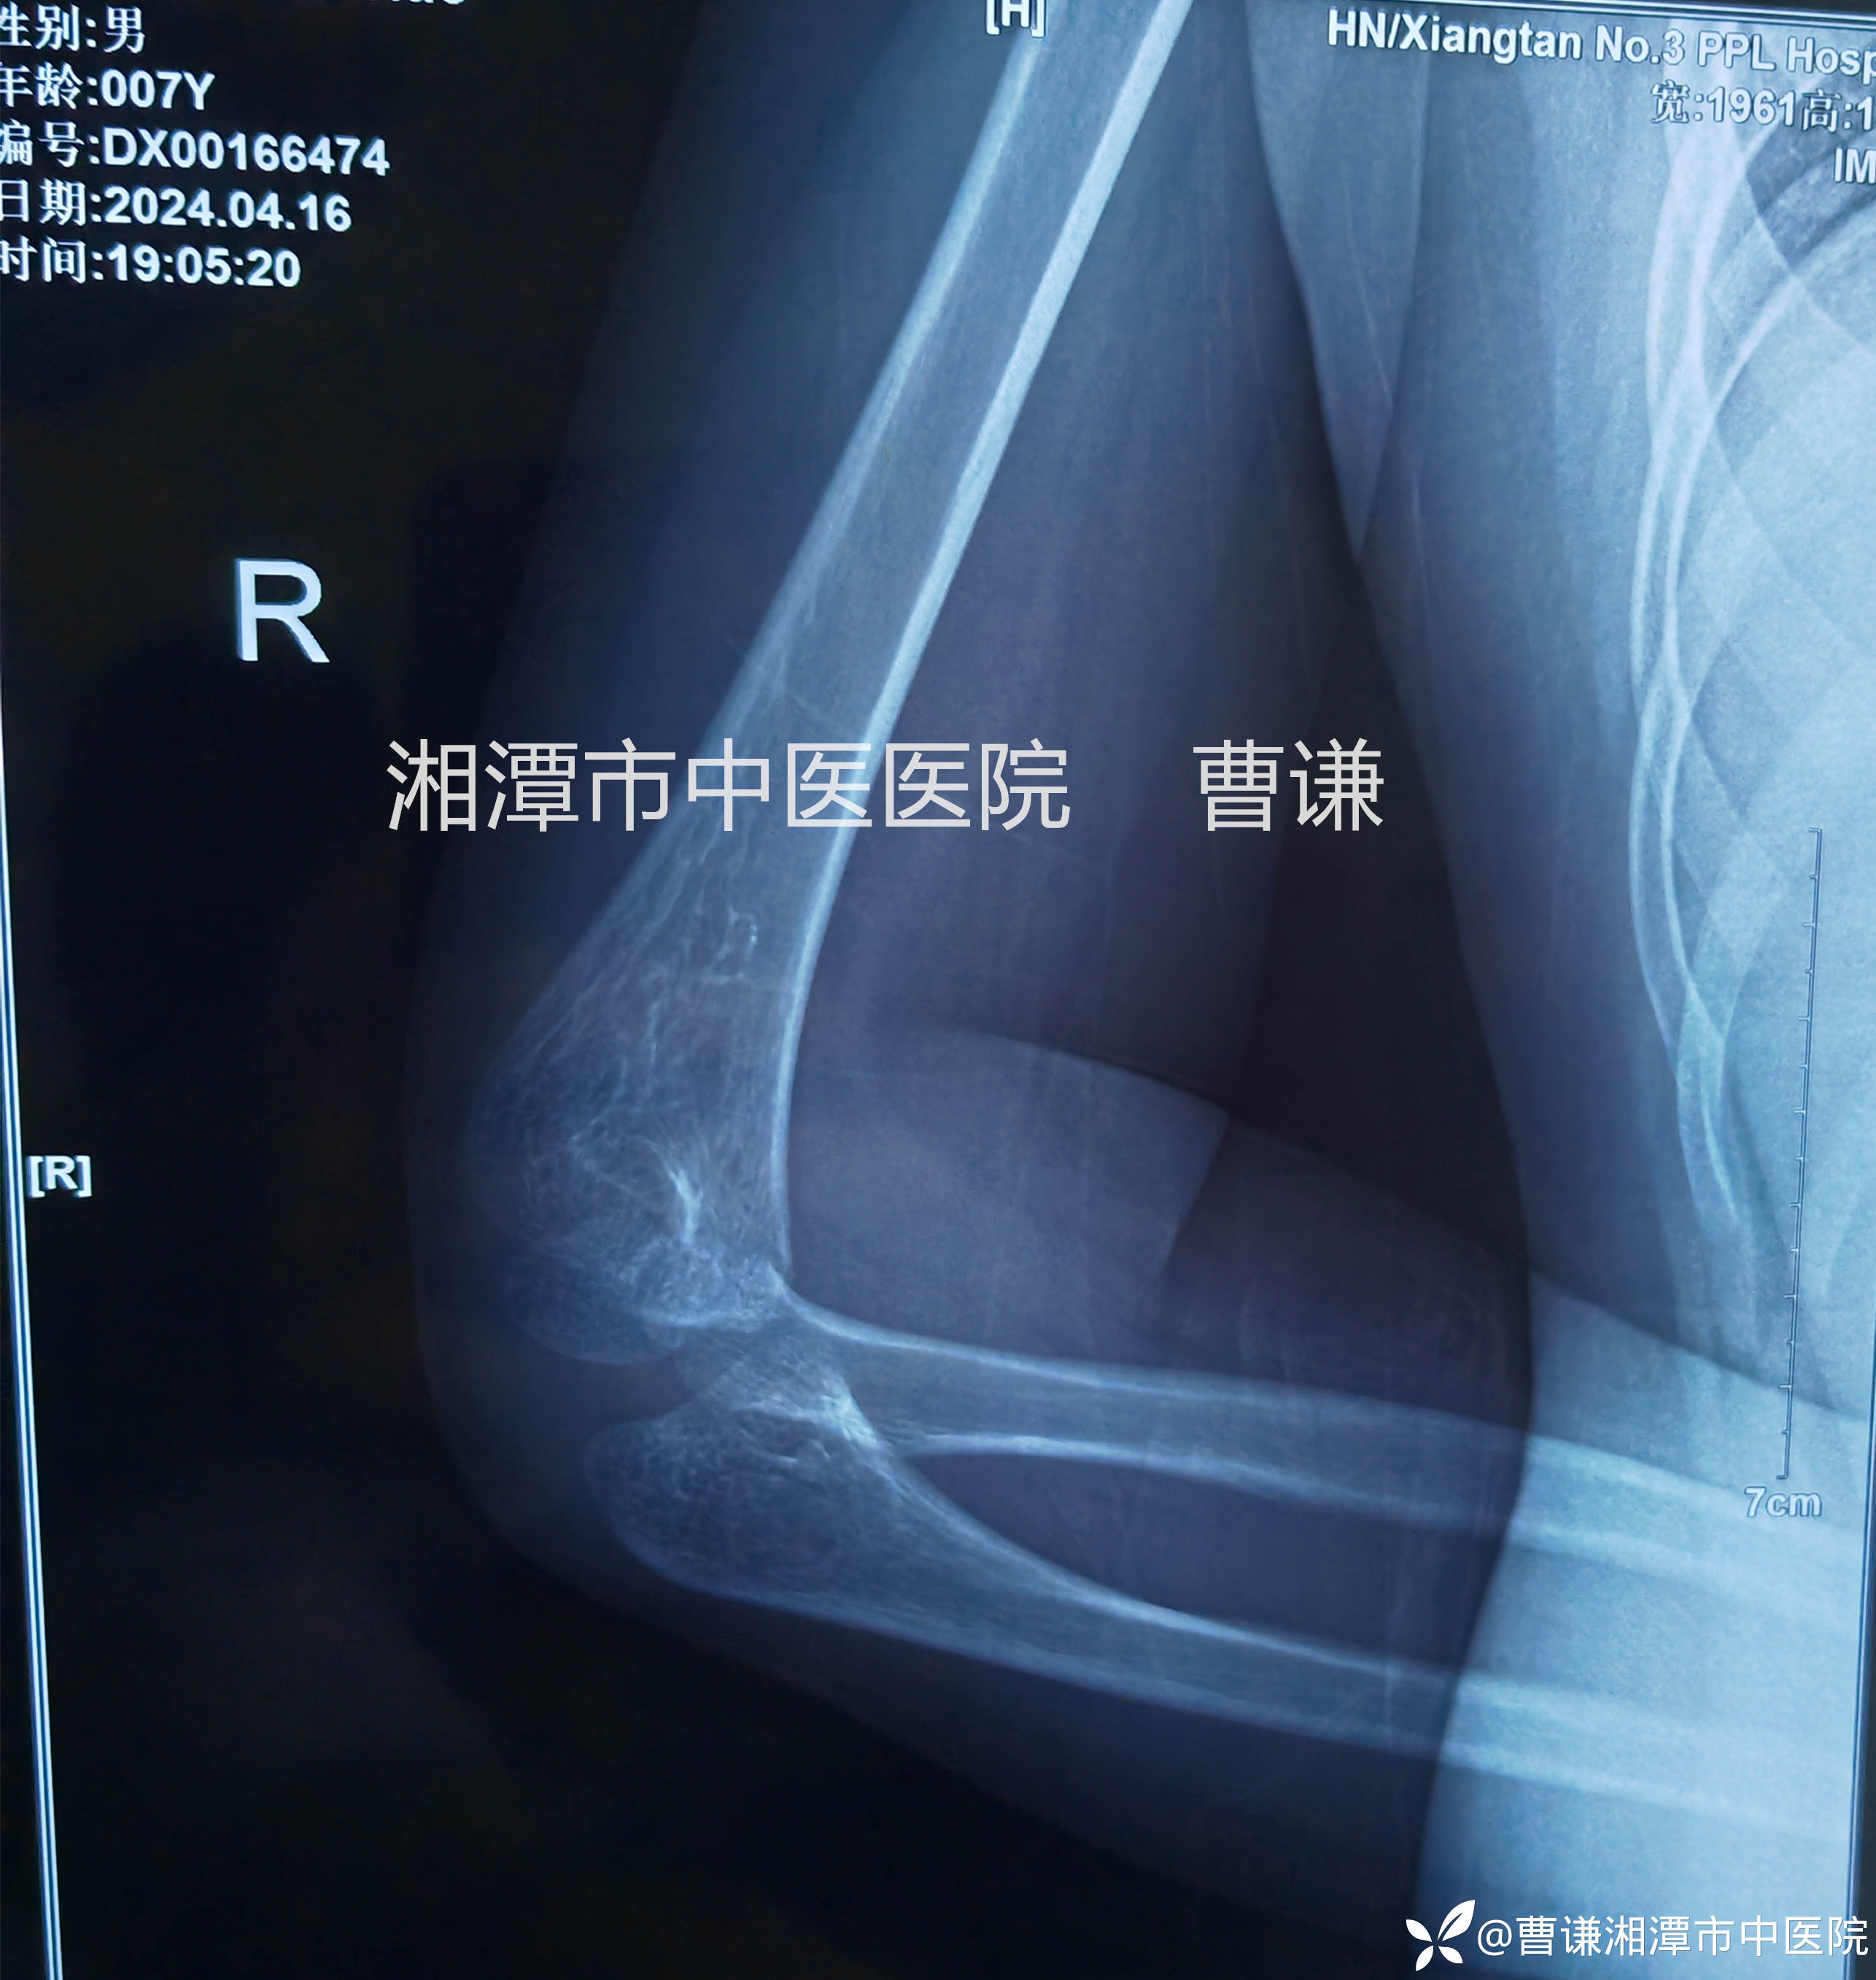

小医生实在没看出啥,还好并不傻,他沿着主任的目光所及之处终于发现肱桡关节匹配不良。再仔细体查患肢肘关节周围压痛,以桡骨头处及尺骨鹰嘴处明显。看来是个隐匿性的孟氏骨折啊!

固定完成拍片复查示肱桡关节匹配良好。